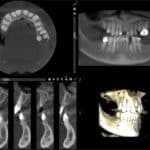

3D Cone Beam CT

Utilizing Planmeca Ultra Low Dose technology, this proprietary 3D imaging protocol enables CBCT imaging with even lower patient radiation dose than a standard panoramic image. 3D imaging plays a vital role in diagnosis of oral pathology and implant planning.